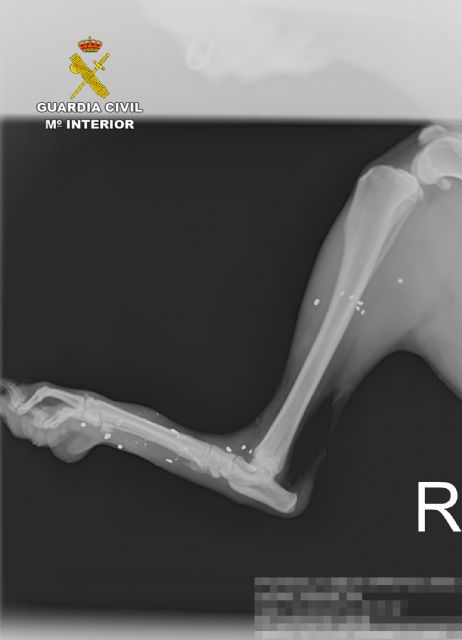

Las primeras pesquisas permitieron constatar que dos de los canes propiedad del denunciante habían sufrido heridas tras ser alcanzados por plomos de cartuchos de caza, según se apreciaba en el informe veterinario y radiológico, en gran parte de su cuerpo. Al parecer, había un tercer perro que aún sigue desaparecido y que se presume que también pudo haber sido alcanzado por los disparos.